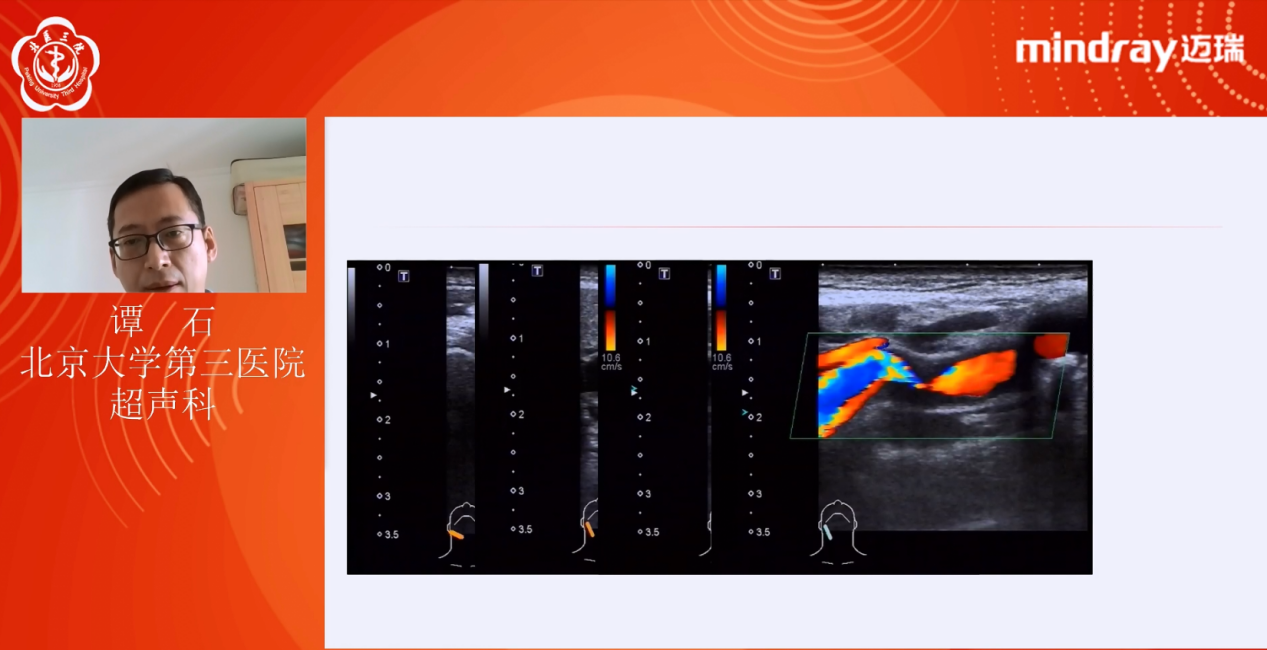

北京大学第三医院超声科谭石副主任医师讲解《颈动脉超声扫查规范与技巧》